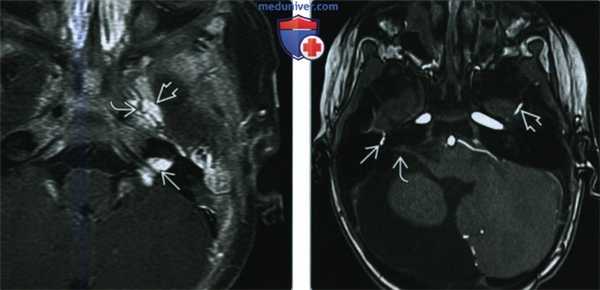

(Слева) При МРТ у мальчика в возрасте трех недель с параличом лица в ВСК слева и кавернозном синусе визуализируются объемные образования, активно накапливающие контраст. В образовании левого кавернозного синуса хорошо видны участки потокового выпадения сигнала. Образование в ВСК имитирует шванному. Такие гемангиомы подвергаются инволюции после первого года жизни.

(Справа) При аксиальной МРА у новорожденной девочки с синдромом PHACES и гипоплазией правого полушария мозжечка визуализируется персистирующая стременная артерия справа. Обратите внимание на нормальную левую среднюю менингеальную артерию. Правый ВСК расширен.

• МРА:

о Гипоплазия/аплазия, аберрантный ход, перегиб, извитость, петлистость, расширение, аневризма ВСА или позвоночных артерий

о Персистирующие фетальные коммуниканты (например, персистирующая стременная артерия)

о Стеноз и окклюзия артерий с формированием коллатералей (моямоя)